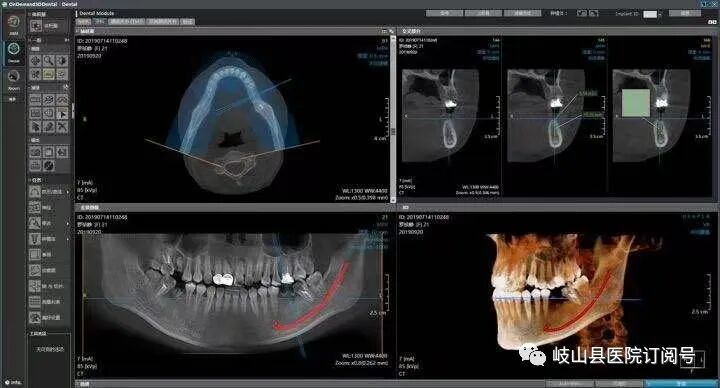

卡瓦CBCT即卡瓦口腔颌面锥形束CT(cone beam computed tomography),其基本原理是X线发生器以较低的射线量(通常球管电流在10毫安左右)围绕投照体做环形数字式投照,然后将围绕投照体多次数字投照后“交集”中所获得的数据在计算机中“重组”,进而获得高清三维图像。卡瓦X-TREND“三合一”CBCT即具有口腔曲面断层片、头颅侧位定位片和多功能CT三种拍摄功能,满足了口腔临床诊断的所有需要。

是目前国际最先进的口腔专用CT,在业界被誉为神奇的“慧眼”,具有扫描快、范围大、精度高、应用广、放射量极低的特点。可以通过其强大的处理软件功能以及面部匹配技术迅速形成清晰逼真的三维图像,较传统CT对于牙齿及颌骨组织的结构成像质量更好,彻底解决了口内牙片机、口腔全景机等口腔X射线设备影像重叠、畸变的问题,可以便捷直观地发现多种牙齿隐患问题,为口腔医生提供了精准的诊断与治疗依据。

卡瓦CBCT广泛应用于口腔各个领域:口腔颌面外科方面用于肿瘤、囊肿的范围及与上颌窦及下颌神经管的关系,颌骨骨髓炎的诊断,骨折的诊断及术前指导,阻生智齿的诊断及拔除指导,多生牙及埋伏牙的定位及毗邻关系,颞下颌关节病的诊断等;牙体牙髓方面可以清晰观察根管的数目及形态、能够发现变异的细小根管、早期的根尖炎症、牙根折裂等情况;牙周病方面可以确定牙周病的病变程度及指导治疗;牙列错颌畸形矫治方面用于研究颅面生长发育,诊断分析、矫治设计、前后对比,头影测量等;口腔种植方面涵盖了种植牙的每一个种植细节,提供了可靠的理论依据,确保种植牙手术的成功率。(口腔科  陈亚萍)